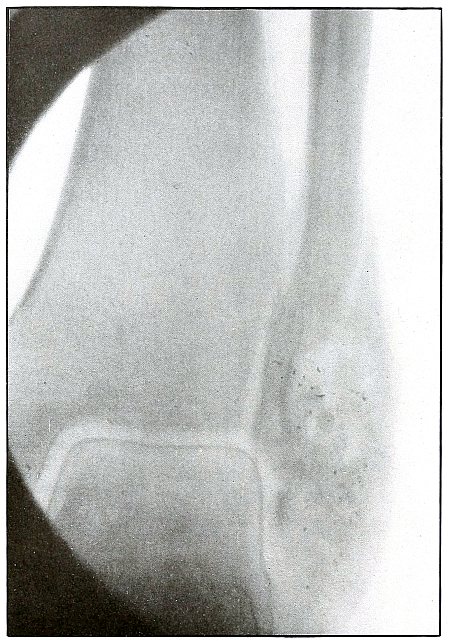

Gunshot fracture, ankle |

154 |